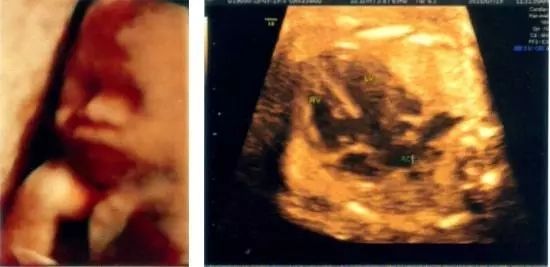

▲脊柱裂,可导致下肢瘫痪,大小便失禁等

▲脑裂畸形,可导致轻度瘫痪,不同程度的癫痫、发育迟缓、智力迟钝,眼盲等症状